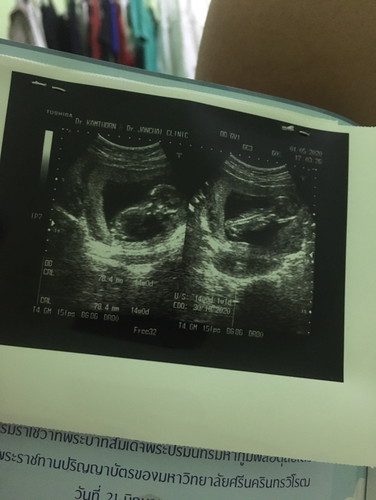

นอนคว่ำแบบนี้ลูกจะเป็นอะไรหรือเปล่าคะ. ไม่หันให้หมอดูเลย. 14 สัปดาห์ กังวลใจ. อันตรายหรือเปล่าคะ

จะเป็นอันตรายต่อเด็กไหมคะ